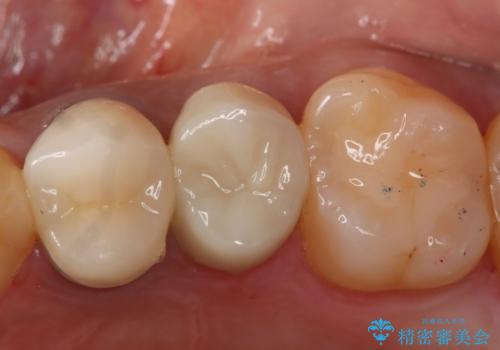

う蝕除去中に露髄 フルジルコニアクラウン

う蝕除去中に露髄したため精密根管治療へと切り替え、仮歯をはさんでセラミッククラウンを装着し終了としました。